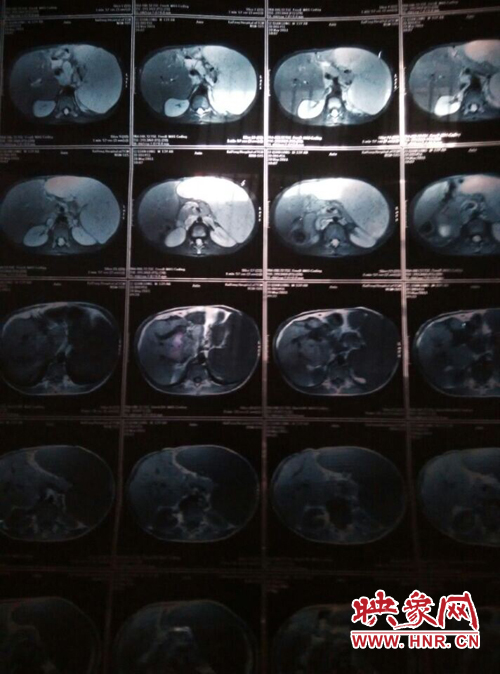

映象網(wǎng)商丘訊(記者 曾巖 代艷)他是一個(gè)花季少年,兩歲半時(shí)患上怪病,經(jīng)過漫長的求醫(yī)之路查出是肝脾腫大,十幾年的看病之路,花了幾十萬,非但沒有醫(yī)好他的病,讓這個(gè)原本就貧困的家庭雪上加霜。

他叫李乾龍,今年16歲,家住寧陵縣城郊鄉(xiāng)李莊村,家里有四口人,目前在寧陵縣黨校就讀上高一,他一邊上學(xué)一邊看病,十幾年來,他們跑遍了大小醫(yī)院,卻一直沒查出他的病因。16歲的他發(fā)育的還沒有13歲的弟弟高,肚子大的像個(gè)皮球,經(jīng)常身體發(fā)熱,全身無力,因?yàn)闆]錢去大醫(yī)院檢查治療只得在家保守治療。